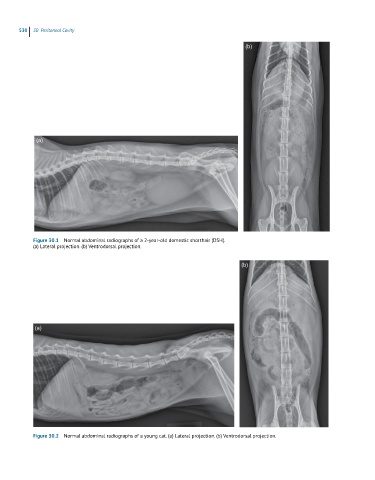

Figure 30.1  Normal abdominal radiographs of a 2-year-old domestic shorthair (DSH).

(a) Lateral projection. (b) Ventrodorsal projection.

Figure 30.2  Normal abdominal radiographs of a young cat. (a) Lateral projection. (b) Ventrodorsal projection.